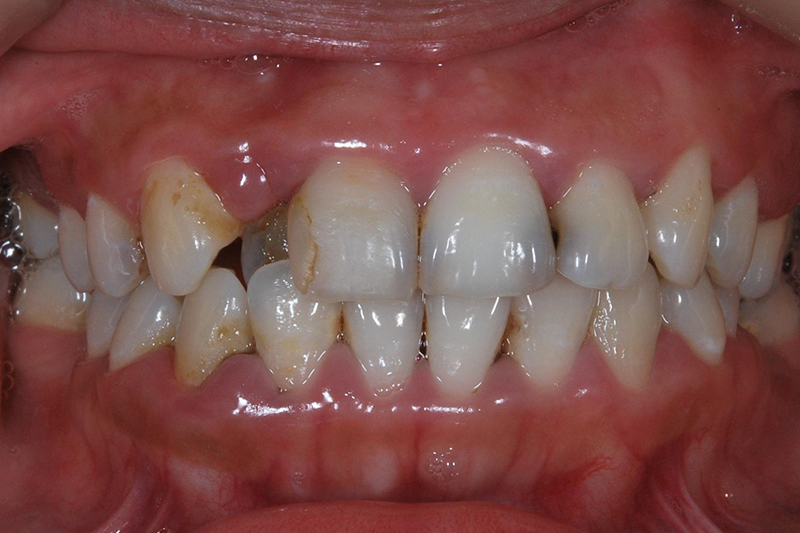

齒列不整

矯正前